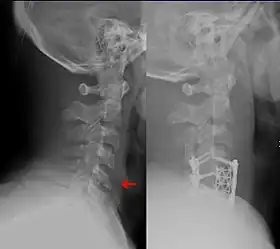

There are multiple devices that can be used in addition to avoiding maneuvers or activities that move the spine.[8][18] Long-term cervical spine immobilization in patients with cervical spine fracture who did not undergo surgery can be performed using a long-term cervical collar (Miami J,[6][8] Philadelphia,[8] or Aspen[8]) or halo traction device.[8][12] When using a traction device such as the halo to hold the spine in place while it heals, this is called closed reduction, as opposed to a surgery which is termed open reduction with internal fixation (ORIF).[18] In general, the halo traction device is preferred for unstable fracture, while the cervical collars are used for neck sprain, stable fracture, or after surgical fixation.[8] Soft cervical collars do not restrict head movement and are more so used for comfort.[8] The sternal occipital mandibular immobilizer (SOMI) can also be used to provide support for cervical spine sprain, stable fracture, or postoperative support.[8]